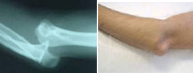

Luxación de codo

Luxación de codoLuxación de codoLa articulación del codo tiene lugar entre el húmero y el cúbito y radio. Tiene lugar con mayor frecuencia en la segunda década de la vida. La separación traumática entre brazo y antebrazo es frecuente en el ámbito deportivo, especialmente en aquellos deportes que pueden provocar impactos sobre la mano con el codo en extensión. Ello es posible en artes marciales, futbol, baloncesto, y escalada entre otros.

Esta lesión no sólo compromete las estructuras óseas sino las ligamentosas y neurovasculares por lo que se requiere un meticuloso estudio en el servicio de urgencias para diagnosticar el grado de afectación tratándolo entonces adecuadamente.

En un primer momento la recolocación del codo en situación anatómica es primordial a través de un suave gesto y en algunas ocasiones bajo anestesia. Si a pesar de la congruencia articular, el codo se presenta inestable, puede ser necesario reforzar la estabilidad ósea con una intervención quirúrgica.